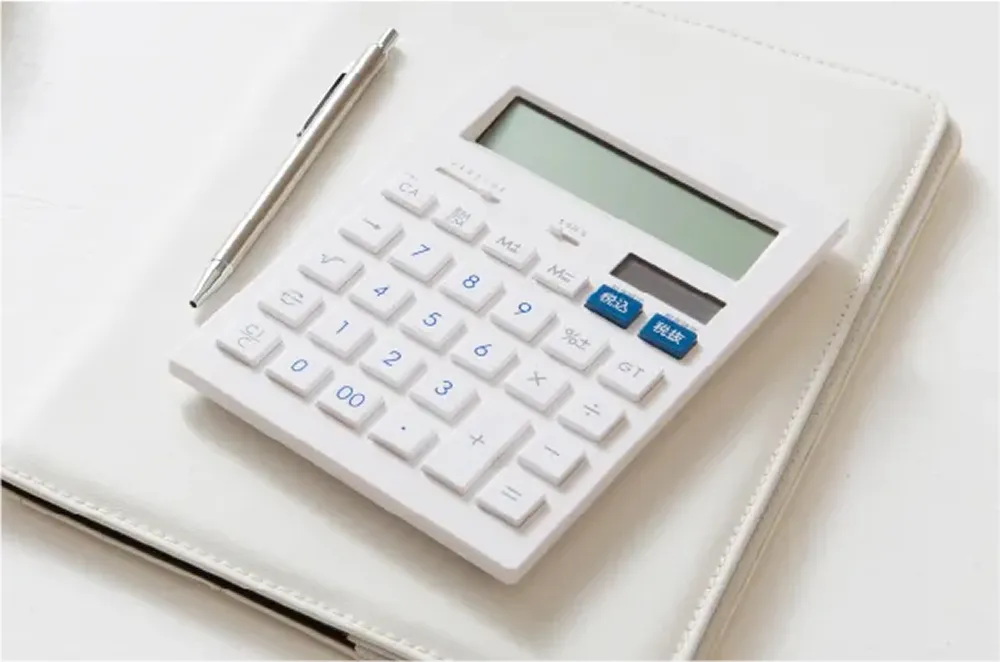

理由3 専用手術室・最新歯科CTなど、安全な治療を支える充実の設備

インプラント治療の安全性は、設備環境にも大きく左右されます。当院では以下の設備を完備し、より安全な治療環境を整えています。

歯科用CT

従来のレントゲンでは把握できなかった骨の厚さ、神経・血管の位置を3次元的に確認できます。最小限の被曝で精密な検査が可能です。

シミュレーションソフト

CT画像をもとに、埋入位置・角度・深さを事前にシミュレーションします。これにより、手術計画をより具体的に立てることができます。

サージカルガイド

シミュレーション結果を反映したマウスピース型の装置です。計画に沿った位置への埋入をサポートします。

当院のインプラント治療の特徴

インプラント治療を成功させるために大切なことは、術前に精密な情報(データ)を取得し、正確な治療計画を実行することです。

当院では「経験や勘」に頼るのではなく、精密機器を活用した「データ」に基づいた安全なオペ体制を整えています。

特徴① 人為的なミスを減らすことを目指した「3Dコンピューターインプラント」

当院では、高解像度CTとシミュレーションソフトを活用した「3Dコンピューターインプラント」を導入しています。

CT画像から神経や血管の位置を3次元的に把握し、コンピューター上で理想的な埋入位置・角度・深さを計画。その計画をもとに「サージカルガイド」というマウスピース型の装置を作製します。

手術時にはこのガイドを使用することで、計画通りの位置に精密にインプラントを埋入することができます。これにより、人為的な誤差を減らし、安全性と精度に配慮した治療を心がけています。

特徴② 切開を抑えることを目指したインプラント治療

従来のインプラント手術では、歯茎を大きく切開して骨を露出させる方法が一般的でした。しかし当院では、精密検査とシミュレーションによって歯茎の中の状態を十分に把握することで、症例によっては歯茎の切開を最小限に抑えることが可能です。

切開を小さくすることで、術後の痛みや腫れが軽減され、患者さんの精神的・肉体的な負担を大幅に軽くすることができます。

※すべてのケースで適用できるわけではありません。精密検査の結果、従来の方法が適切と判断される場合もあります。